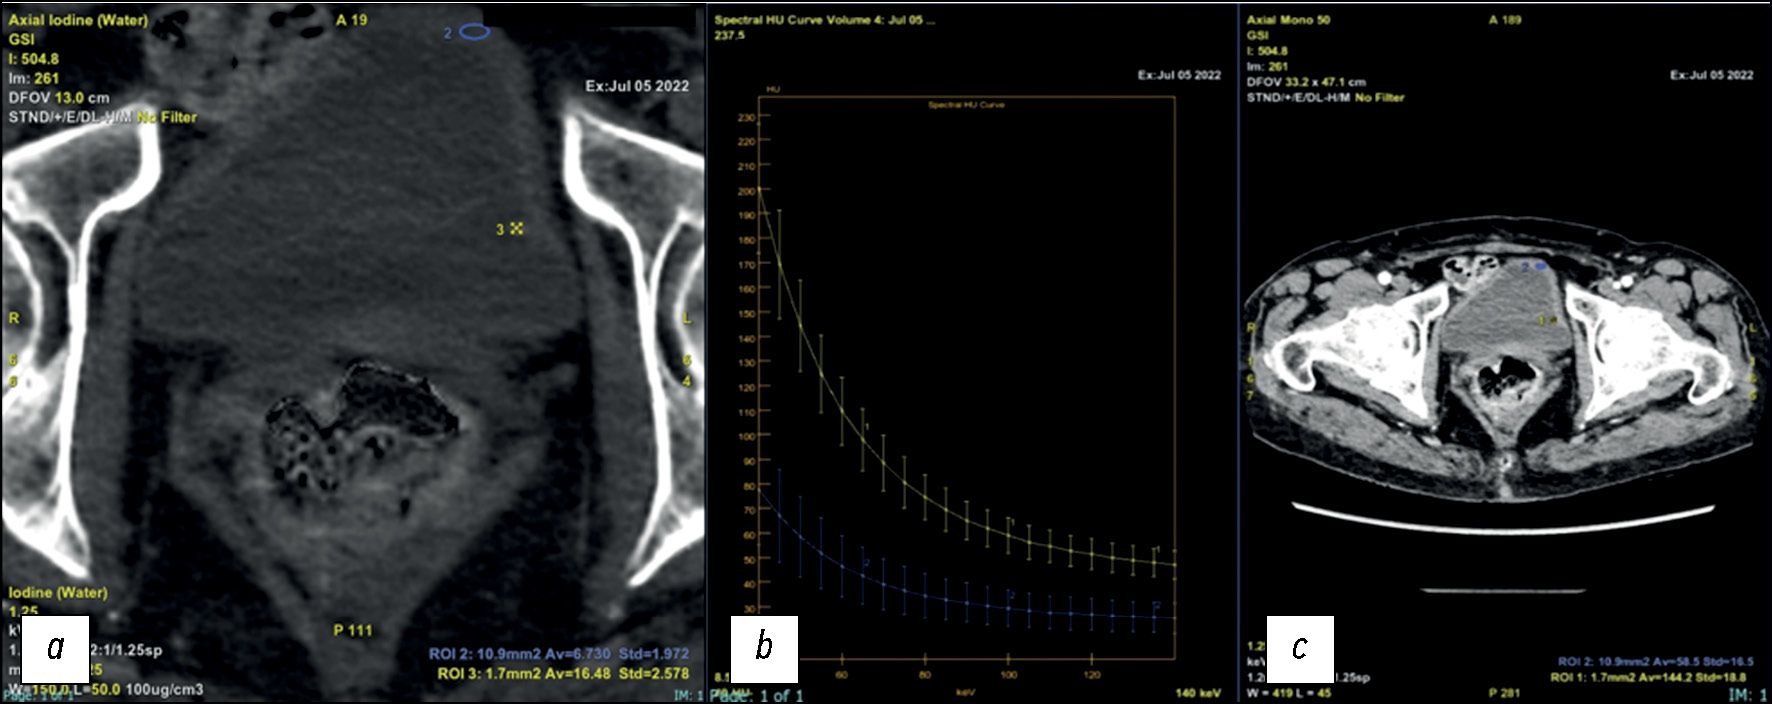

Спектральная кривая благодаря её свойствам подходит для более точного описания очага. Например, кривая, построенная для узлового образования стенки мочевого, идёт к максимуму при более низком уровне энергии в кэВ (рис. 4).

Рис. 4. Спектральная кривая позволяет более точно установить характеристики материала, поскольку кривые затухания у разных материалов отличаются. С помощью воздействия при разных уровнях энергии можно дифференцировать материалы на основании различий в коэффициентах затухания одного материала.

Рис. 7. Пациент с гематурией с подозрением на опухолевый очаг в мочевом пузыре: a — при проведении компьютерной томографии в аксиальной плоскости наблюдается умеренное утолщение стенки мочевого пузыря со значительной концентрацией йода, что с высокой вероятностью указывает на присутствие очага. AV отражает концентрацию йода в мг/мл, которая составляет 6,7 и 16,48 мг/мл для участков, отмеченных синим кругом и выделенных жёлтым (пороговое значение 1,3 мг/мл) соответственно; b, c — спектральная кривая, которая позволяет описать материалы по различиям в кривой затухания.